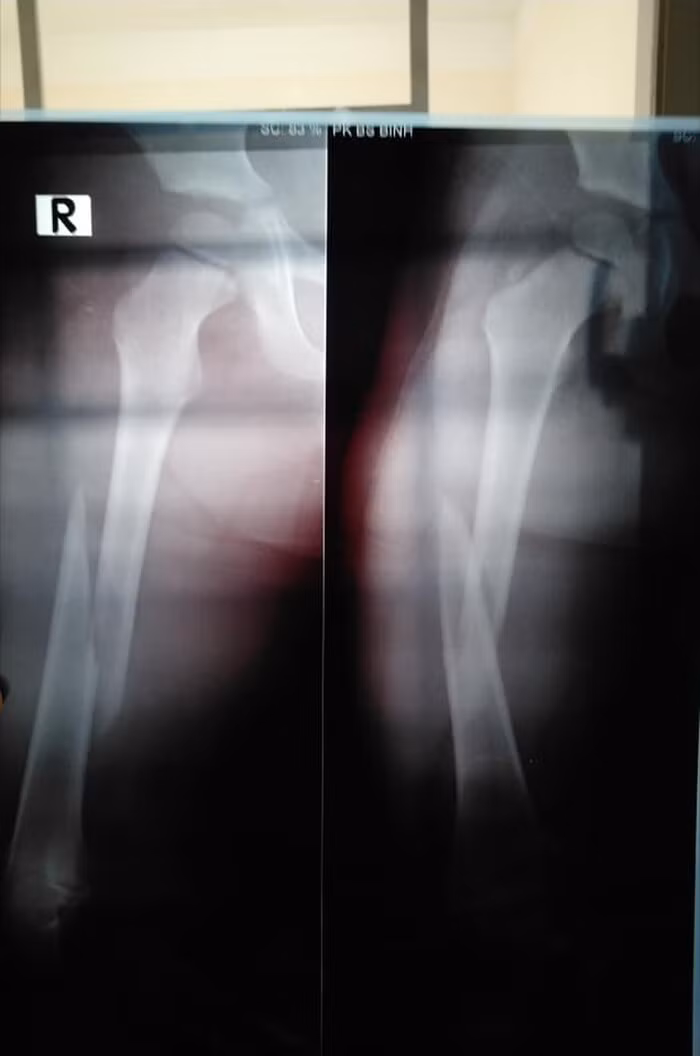

Theo chị C., kết quả chụp X-quang cho thấy con bị gãy xương đùi. Trường hợp của con nghiêm trọng nên các bác sĩ khuyên gia đình cần chuyển gấp lên Bệnh viện Nhi Đồng.

Tại đây, các bác sĩ cho biết, bé P. phải nằm kéo chân đến lúc xương liền lại mới bó bột, cần phải nằm viện ít nhất từ 12 - 14 ngày. Sau khi bó bột xong, bé P. cần thời gian dài tập vật lý trị liệu.

Kết quả chụp X-quang cho thấy bé P. bị gãy xương đùi.